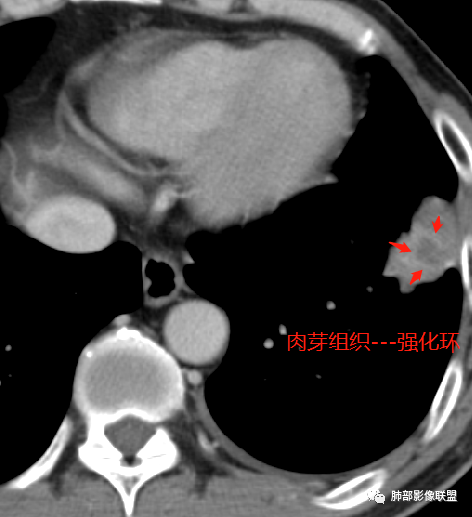

左肺下叶前基底段肿块,分叶状,边缘平直凹陷,部分膨隆。支气管进入后截断,宽基底与胸膜相连,内部坏死,周围有小卫星灶,强化见坏死区周围环形高密度,首先考虑良性,肉芽肿,结核?鉴别腺癌。

增强坏死周围似乎见环形强化的环

第三,强化有环形强化的感觉,坏死区太圆太规整。